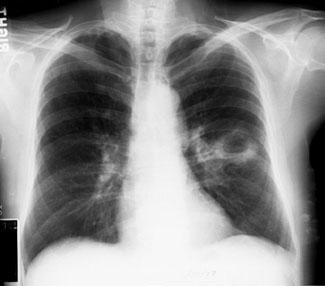

是肺实质坏死形成的亚急性感染。常累及右肺,多于左肺,并且最常见于吸入口咽分泌物之后。肺脓肿表现缓慢,隐匿,通常在初次误吸1-2周后发展。下图显示了肺脓肿。

图1 厚壁肺脓肿

胸部X线检查可诊断和区分肺炎,肺脓肿和脓胸。肺脓肿和肺炎需要药物治疗,而脓胸经常需手术治疗。胸部X线片如下所示。

图4 肺炎球菌性肺炎并发坏死和脓肿

图5 胸部X线片显示肺脓肿的气液平面特征

在胸部X线片上,肺脓肿表现为孤立的空洞,具有气液平面。周围斑块状浸润有助于区分肺脓肿与空洞性肺癌。

在胸部X线片,发现脓胸而不是肺脓肿的气液平面向胸壁延伸,气液平面跨过肺裂延伸,并逐渐变细。

胸部X线片上应仔细检查肋膈角,以评估预示积液或脓胸的液体是否出现。